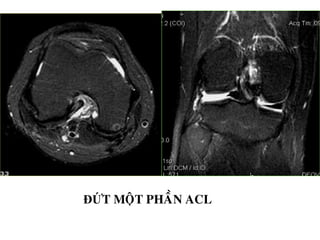

ĐỨT MOÄT PHAÀN ACL